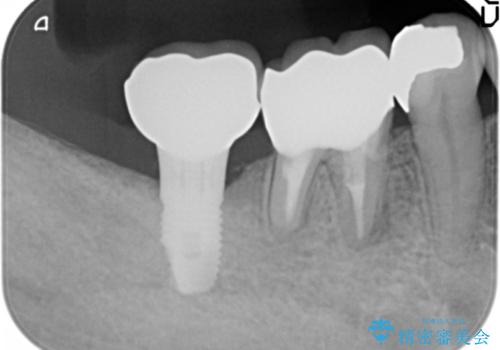

骨が少なくインプラントできないと言われた 下の奥歯のインプラント 60代男性

- 奥歯のインプラントをご希望し来院された患者様です。

骨が少なく下顎神経に近いことから、他院でインプラントできないと言われたとのことでした。

骨増生(GBR)を行い骨を増やすことでインプラント治療を可能にしました。

自然な見た目と咬み心地にご満足頂けました。

他院では難しいと言われていたインプラント治療が可能になり、喜んで下さいました。

インプラントの種類:スプライン ツイスト (HAコーティング)

固定様式:セメント固定

クラウンの種類:オールセラミッククラウン スタンダード